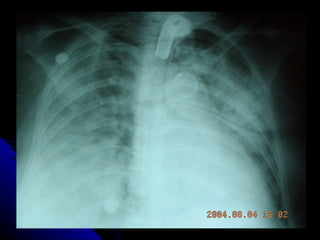

RADIOLOGIA Los infiltrados pueden ser muy pequeños y difíciles de apreciar especialmente en radiografías portátiles. La pausa inspiratoria es prácticamente imposible cuando el paciente se encuentra en ventilación mecánica haciéndolas menos específicas para el diagnóstico. La Tomografía Axial del tórax puede diagnosticar hasta en un 26% más, infiltrados pulmonares a más de definirlos más exactamente que la placa simple del tórax

RADIOLOGIA Los infiltradospueden ser muy pequeños y difíciles de apreciar especialmente en radiografías portátiles. La pausa inspiratoria es prácticamente imposible cuando el paciente se encuentra en ventilación mecánica haciéndolas menos específicas para el diagnóstico. La Tomografía Axial del tórax puede diagnosticar hasta en un 26% más, infiltrados pulmonares a más de definirlos más exactamente que la placa simple del tórax